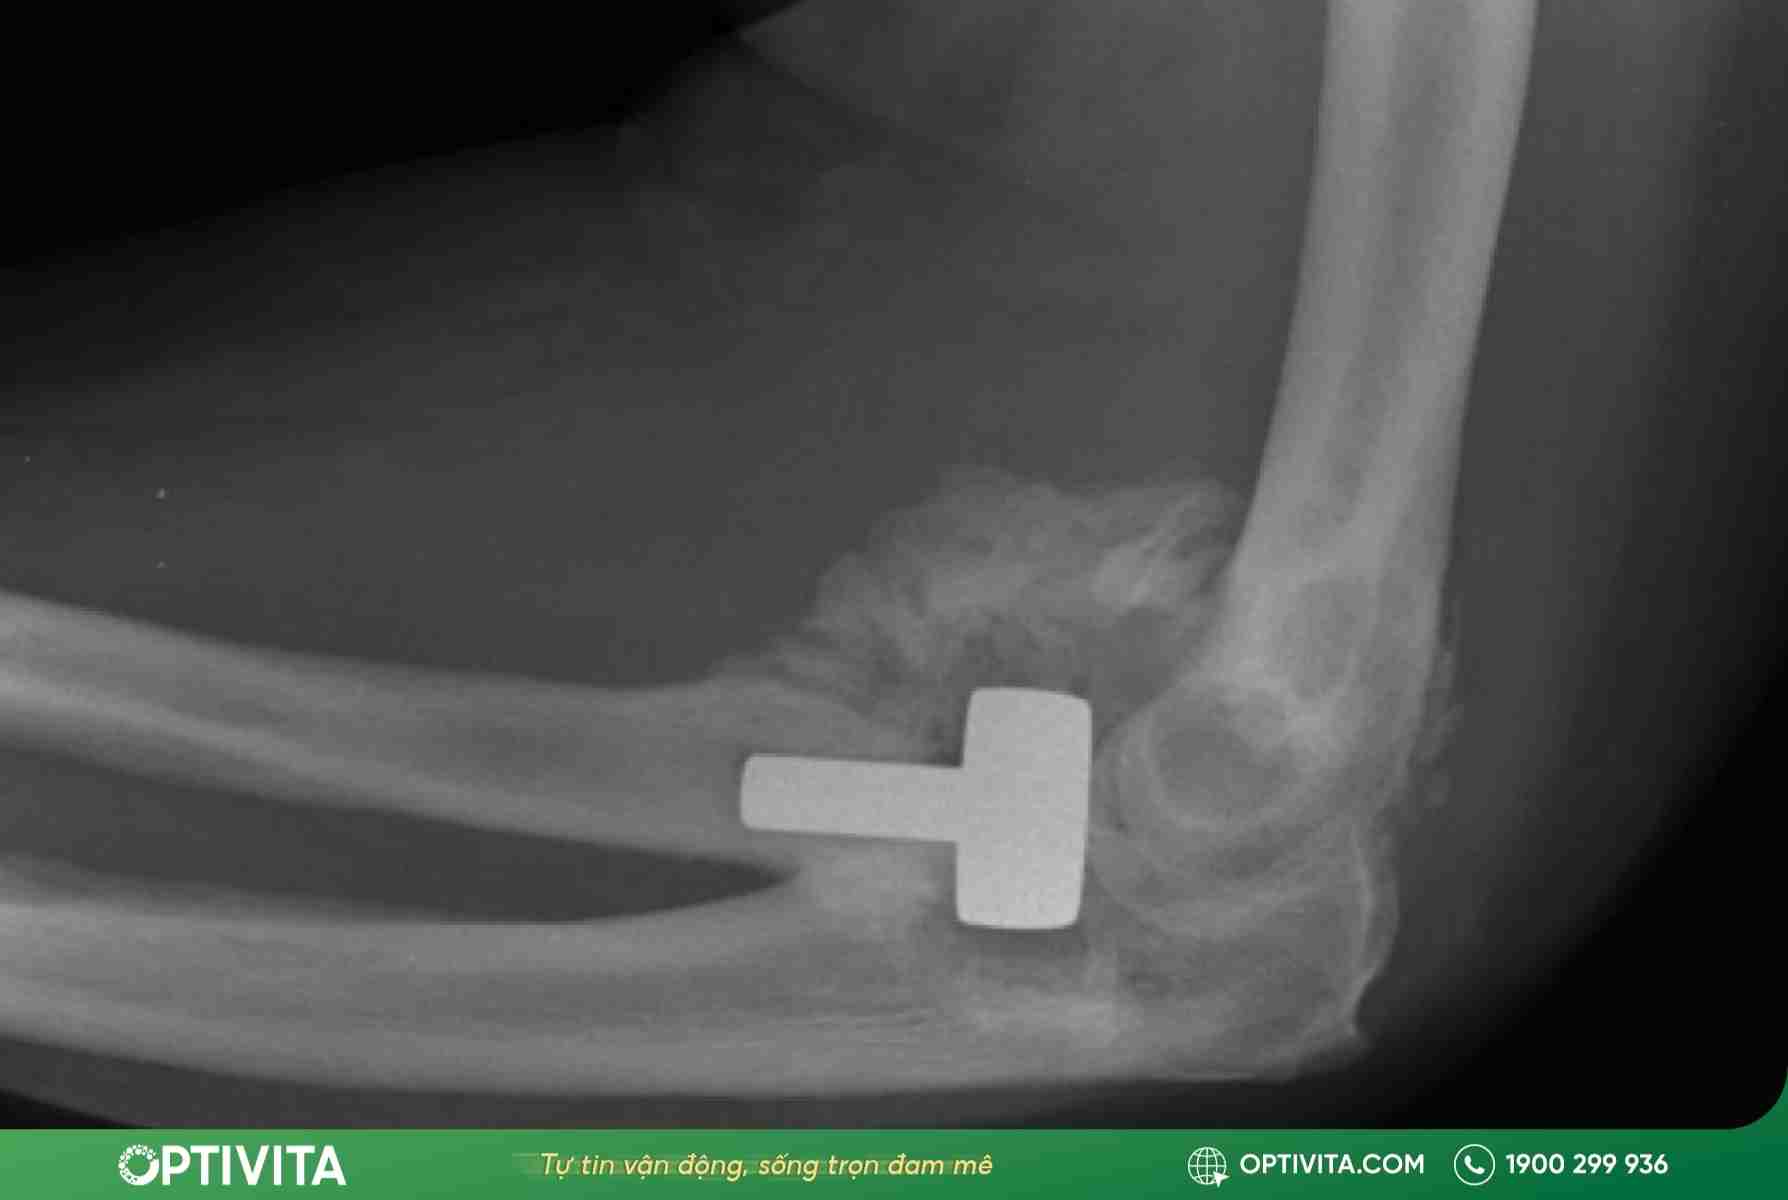

Phẫu thuật (Surgery)

Phẫu thuật là chỉ định bắt buộc trong các trường hợp phức tạp đe dọa chức năng chi:

- Trật khớp kèm gãy xương nghiêm trọng (gãy mỏm vẹt, gãy chỏm quay) gây mất vững.

- Tổn thương mạch máu cần khâu nối hoặc ghép mạch gấp.

- Nắn chỉnh kín thất bại do có phần mềm (dây chằng, cơ) bị kẹt vào khe khớp.

- Trật khớp khuỷu cũ (đến muộn sau vài tuần) không thể nắn kín được nữa.